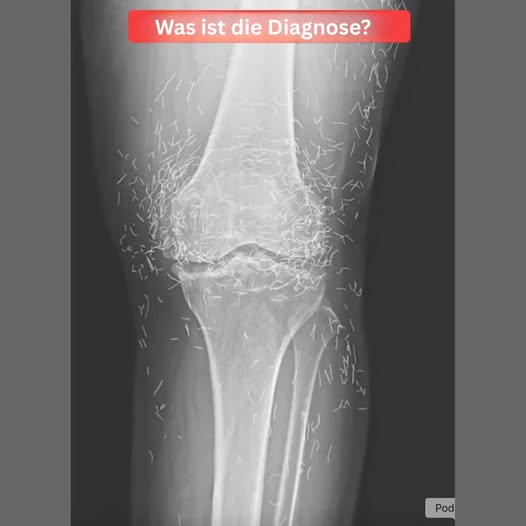

Als eine 65-jährige Südkoreanerin wegen Knieschmerzen zum Arzt ging, erwarteten die Ärzte nicht, auf Gold zu stoßen. Aber genau das taten sie..

Akupunktur, eine jahrhundertealte alternative Behandlung, beinhaltet das Einstechen von Nadeln in den Körper an bestimmten Punkten, um Schmerzen zu lindern oder Krankheiten zu behandeln. In diesem Fall wurden die Nadeln – vermutlich aus Gold – absichtlich in ihren Knien gelassen für anhaltende Stimulation.

Er warnte auch, dass eingebettete Nadeln Röntgenaufnahmen erschweren können. „Die Nadeln können einen Teil der Anatomie verdecken“, sagte Guermazi 2013.

Noch besorgniserregender ist, dass im Körper verbliebene Nadeln zukünftige medizinische Bildgebung gefährlich machen können. „Der Patient kann nicht in ein MRT, weil sich im Körper verbliebene Nadeln bewegen und eine Arterie beschädigen könnten“, fügte Guermazi hinzu.